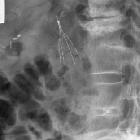

Specific technical steps may vary according to personal preference and on the type of filter being used. Generally, internal jugular or femoral vein is punctured under ultrasound guidance and a guide wire is placed in the IVC. A venogram is obtained by injecting contrast through a multisidehole catheter positioned in lower IVC or distal common iliac vein. The venogram is used to reassess the IVC for patency, size and anomalies. The location of the renal veins is often indicated by the presence of contrast reflux or flow voids. The venous access is dilated using a dilator. The vena cava filter is subsequently deployed in a suitable location through a delivery sheath, typically the infra-renal IVC. Another venogram is obtained to ensure satisfactory deployment of the filter. The delivery sheath is removed. Hemostasis is secured using manual compression.